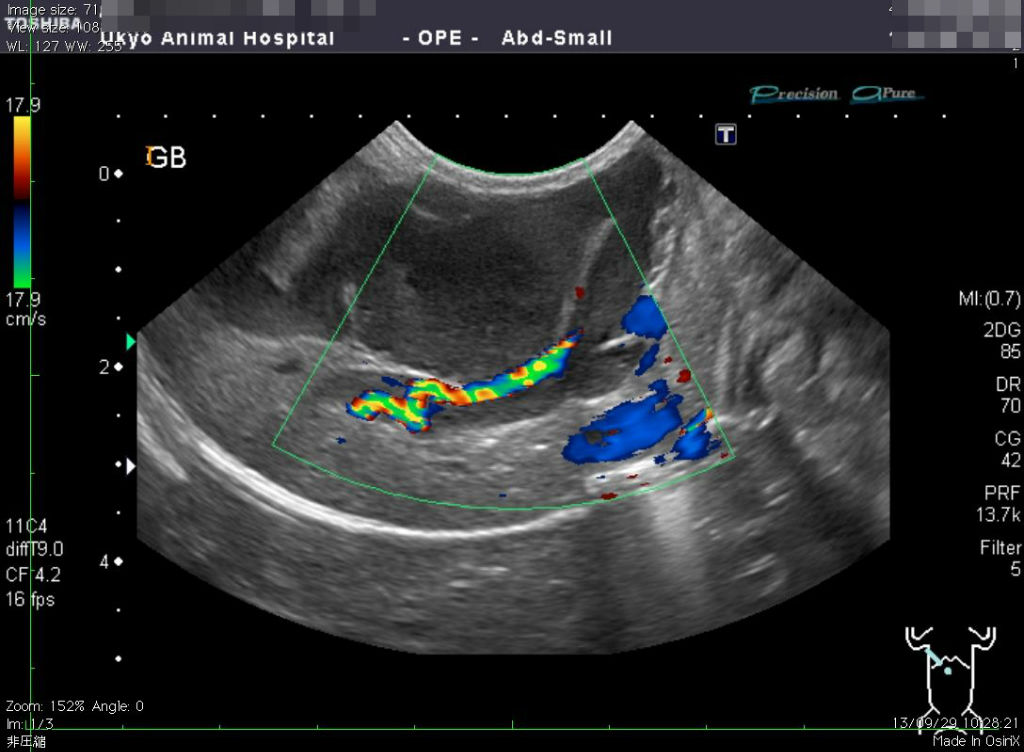

超音波検査で非常に拡張・蛇行した胆管・胆嚢(たんのう)が確認できました

胆嚢の中には胆汁というビリルビンを多く含んだ液体が含まれているのですが

この胆汁がスムーズに流れることができなくなってしまい

胆管閉塞を起こした結果、黄疸という症状が出てしまっていました